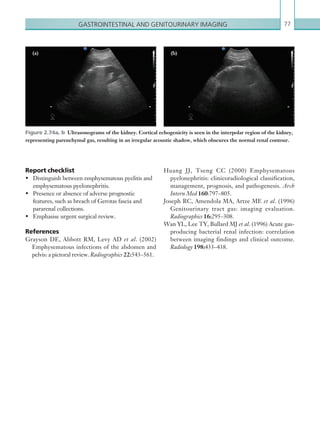

Hormone replacement

therapy.

Miscellaneous Chronic obstructive

pulmonary disease.